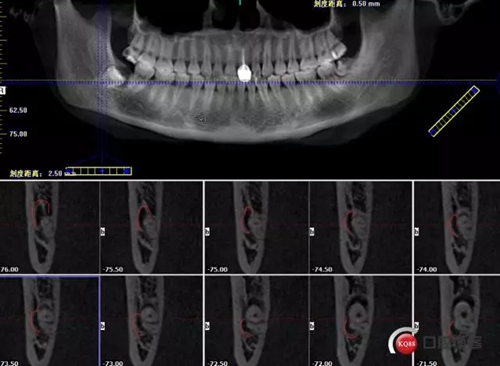

1498615727_411668.png

牙齒下1/3神經(jīng)管在頰側(cè)